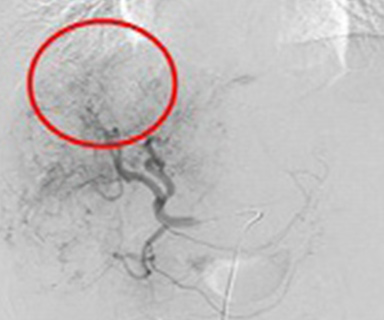

脳動脈瘤(3D画像)

脳動脈瘤

(内頸動脈後交通動脈分岐部)

治療後(コイル塞栓術)

プラチナ製コイル

またクモ膜下出血の原因となる脳動脈瘤や動脈や静脈の異常血管(脳動静脈奇形など)をプラチナ製の針金(コイル)を詰め、血流を遮断して治療することができます。